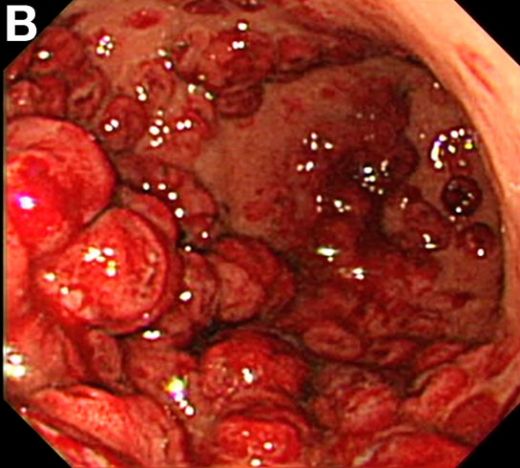

Hemoroid Kanaması Belirtileri ve Tedavisi